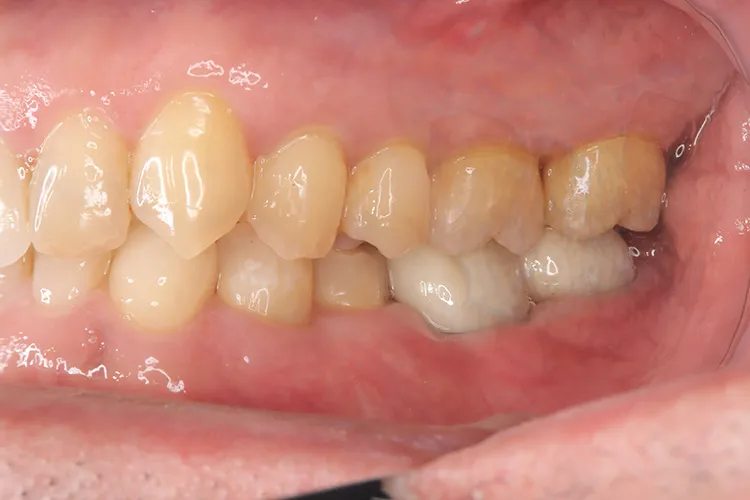

レントゲン画像

治療内容

第一大臼歯1歯欠損をインプラントで回復したケースです。第一大臼歯は永久歯の中で一番最初に生える歯ですが、一番早く傷んでしまう歯でもあります。噛む力の60%を負担し噛み合わせの安定に大きく影響しますので、この歯が欠損すると噛み合わせに悪い影響を与えてしまいます。インプラントで治すことにより噛み合わせが安定するだけでなく、ブリッジのように隣在歯を削らないので天然歯の寿命を延ばすメリットもあります。